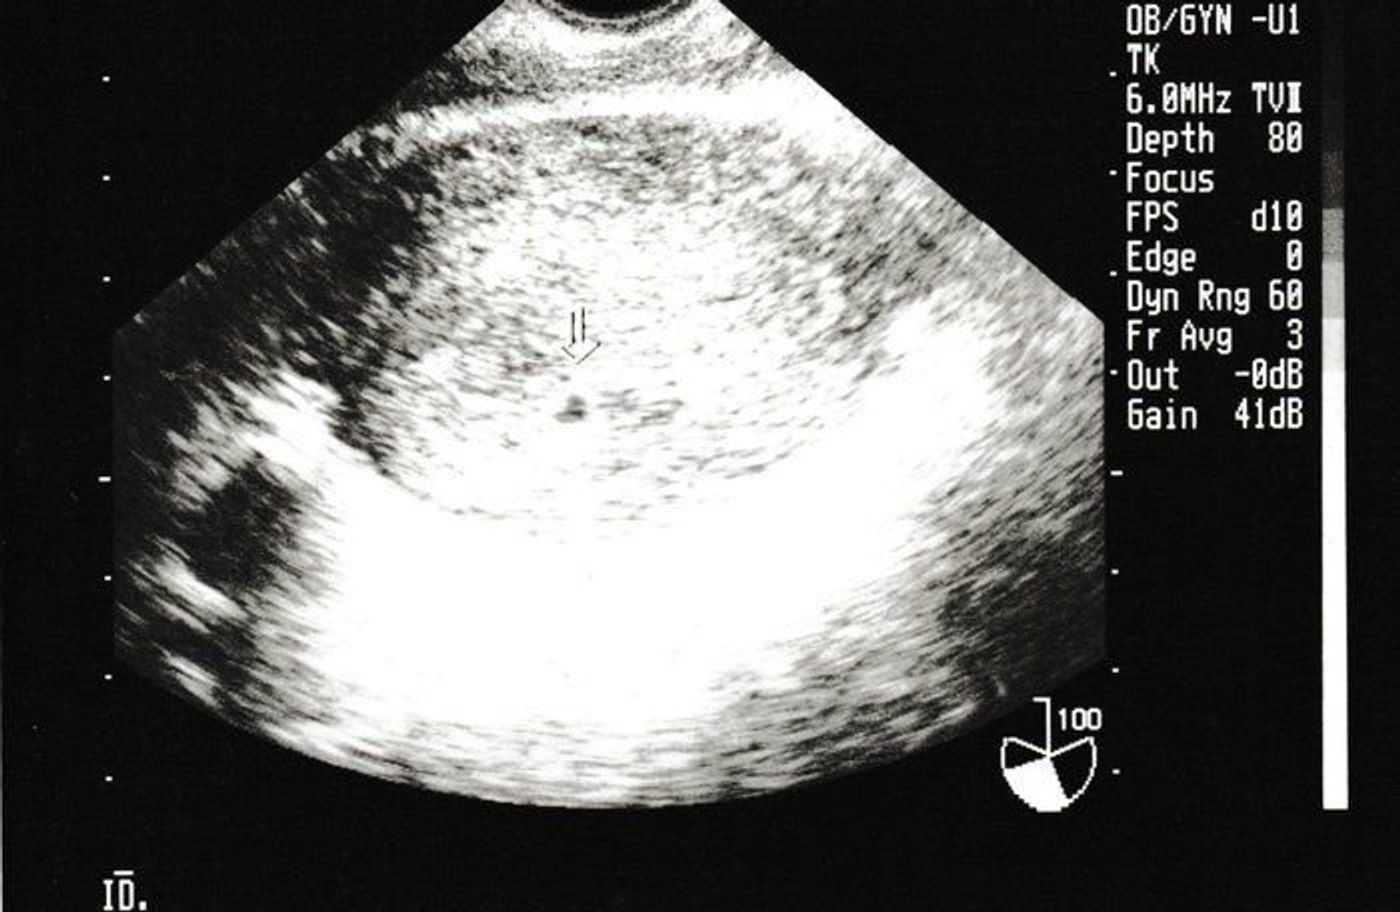

4週 エコー 胎嚢-胎嚢の大きさ(赤ちゃんが入っている袋の大きさ) 上記エコー写真ですと4週1日目ということになります。 妊娠4週目 受精卵が無事に着床して胎嚢が成長を始めています。胎嚢は赤ちゃんが入る袋のことで、早ければ妊娠4週のはじめに確認でき、一般的には 妊娠4週末から妊娠5週頃 までに見えます。 胎芽は妊娠6週頃に確認できたというケースが多く、心拍は早ければ妊娠5週のはじめ・妊娠8週までには全ての妊婦さんに見られ

子宮内に胎嚢が確認できるのは、早ければ、胎嚢が直径2mmくらいになる妊娠4週後半ごろから。 妊娠5週ごろまでは1日1mmのペースで大きくなっていき、6週ごろには確認できることが多いようです。 妊娠5週ごろの様子 胎嚢の大きさは1cm前後。 生理がこない、基礎体温が上がったままで妊娠に気づき始める 市販されている多くの妊娠検査薬の使用期間は、生理予定日の1週間後を推奨しているので、妊娠4週の最後の頃、5週目に入る頃には検査で陽性反応が出る可能性が高くなってきます。 この時期の赤ちゃんは「胎芽」と呼ばれる時期で、目では確認できない大きさです。 赤ちゃんを包む胎嚢という袋が 31 7週0日(胎嚢) (妊娠2ヶ月) 32 10週0日(赤ちゃん現れる) (妊娠3ヶ月) 33 12週0日(頭の形がわかる) (妊娠4ヶ月) 4 実際のエコー写真:妊娠中期 (妊娠5ヶ月~妊娠7ヶ月) 41 16週0日(3Dあり) (妊娠5ヶ月) 42 19週6日(各部位の測定開始

これがこの時もらったエコー写真です。子宮だけ写ってる。。 一般的には、4週後半から5週前半に胎嚢が確認でき、5週後半から6週前半で胎芽や心拍の確認ができる そうです。 となると、5週2日の私は胎嚢が確認できるはずだったのですが。 エコー写真では、GS (gestational sacの略)と表記されます。 一般的に、胎嚢は妊娠4週後半~5週頃にかけて確認することができるとされています。 通常は、胎嚢・胎芽・心拍の三つを確認できた時点で、正常妊娠であると診断されます。 ただし、胎嚢が確認8週4日のエコー写真で胎嚢の隅っこに赤ちゃんがいましたが同じような方いらっしゃいますか😢? 胎嚢も少し長く何が正常なのかわからないので不安です(;_;) 1月16日 お気に入り 妊娠8週目 赤ちゃん 胎嚢 エコー写真 みいぽん 酢 (3